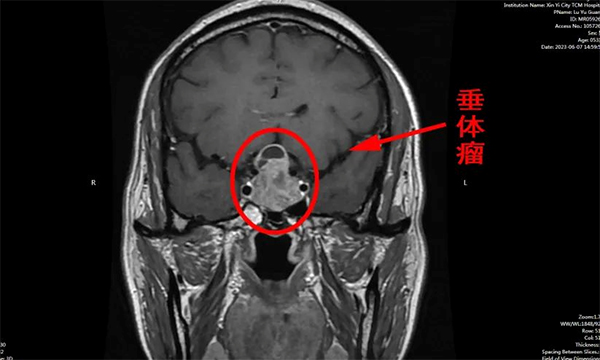

▲ 術前頭部MRI示:垂體瘤

陸先生因無明顯誘因突發(fā)頭痛眩暈不適,伴頭暈、頭脹、惡心、嘔吐癥狀,急來中醫(yī)院神經(jīng)外科謝宏剛團隊處就診。頭部MRI示:雙側(cè)篩竇粘膜肥厚,有23×20×36mm垂體大腺瘤。符合手術指征,在與家屬溝通后進行了充分的病情討論后,謝宏剛團隊決定為患者行“神經(jīng)內(nèi)鏡下經(jīng)鼻—蝶竇垂體病損切除術”。